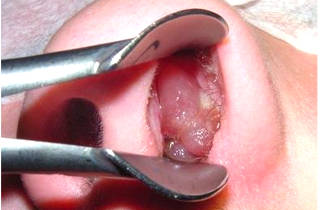

Эти проявления действительно напоминают грипп или ОРВИ. Спустя один-два дня симптомы исчезают, и на губах или слизистой носа возникает сильный зуд и жжение. Через несколько часов появляются маленькие пузырьки, наполненные прозрачной жидкостью.

Когда пузырьки лопаются, на их месте образуются болезненные язвы. Если не расчесывать их, они вскоре подсыхают и покрываются плотной корочкой. Эта корочка может оставаться до нескольких дней, а затем самостоятельно отпадает. Начинается период ремиссии, и вирус не проявляет себя до следующего обострения.